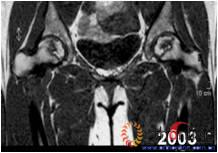

图3-1 女,31岁,SARS患者骨坏死,(1)MRI示双侧股骨头坏死,右Ⅱb(B型),左Ⅱc(C1型);(2)打压植骨术(未加BMP2)后坏死修复不完全,仍遗留股骨头软骨下病灶未完全修复, 5年随访关节功能优(Harris评分96分)

图3-2 女,30岁,SARS患者骨坏死,(1)术前MRI示双侧骨坏死;右Ⅱc期C3型,左Ⅱb期B型,打压植骨术(加BMP2),(2)5年后CT显示病灶修复好,关节功能优